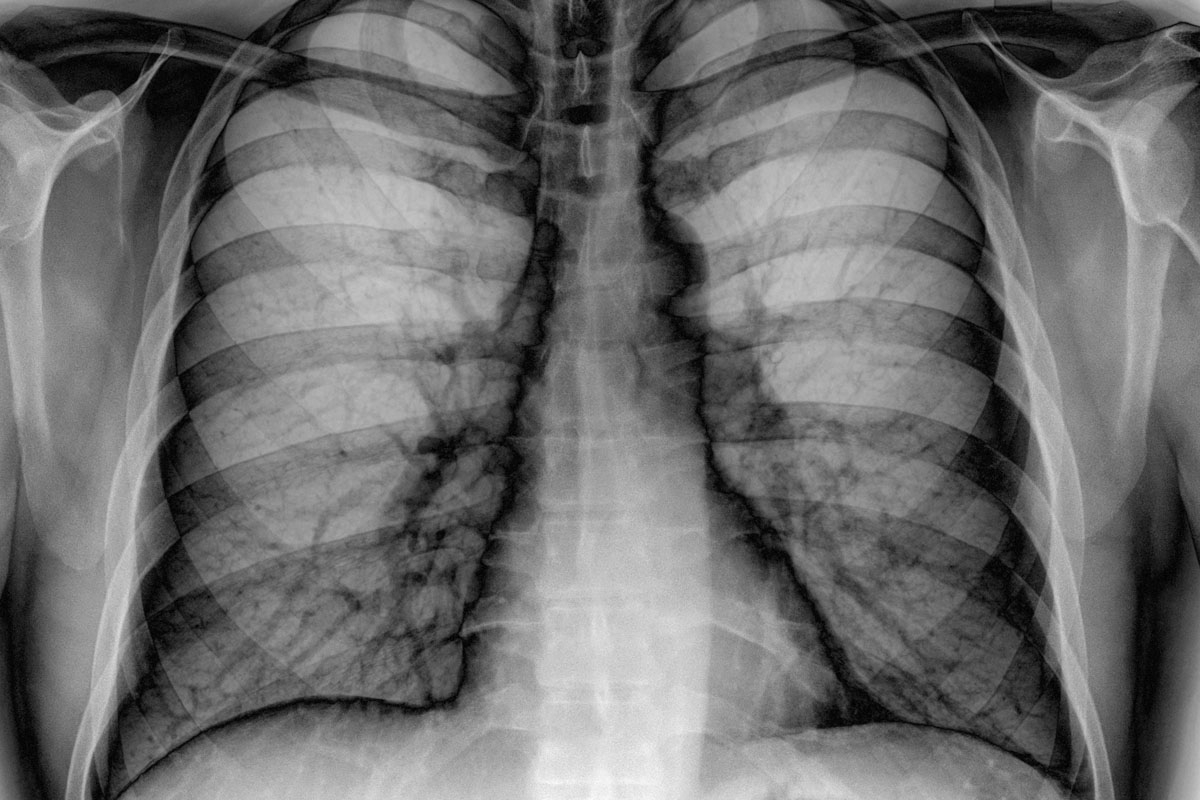

На сегодняшний день многих женщин интересует, насколько целесообразна и безопасна флюорография при грудном вскармливании. Флюорография как стандартизованный метод диагностики помогает быстро, легко и безболезненно обнаружить большое число патологий, таких как пневмония, туберкулез, а также другие заболевания легких на самых различных стадиях.

Достаточно часто возникают ситуации, когда кормящей маме предлагается сделать флюорографию (сокращенно флг). Флюорографическое исследование позволяет выявить множество заболеваний даже на ранних стадиях. Это такие недуги, как: туберкулез легких, онкологические и другие заболевания. Данные опасные болезни необходимо лечить незамедлительно, поэтому процедура может быть назначена уже в роддоме после родов, при поступлении на работу или же в качестве планового диагностирования.

Особенности флюорографического исследования

При процедуре флюорографии рентгеновское излучение проникает сквозь тело, и благодаря чему осуществляется фотографирование изображения. Это изображение отображается на специальном экране, что позволяет специалисту получить данные о состоянии внутренних структур. Посредством этого метода исследования можно выявить многие нарушения внутренних органов.

Флюорографическое исследование помогает выявлять опасные заболевания даже на начальных стадиях. Флюорография совместима с грудным вскармливанием и никаких отрицательных воздействий не оказывает, разовая доза облучения при флюорографии не окажет воздействия на грудное молоко, однако поможет врачам поставить верный диагноз. Рентгеновское излучение не проникает в грудное молоко, поэтому кормить ребенка после процедуры рентгена можно.